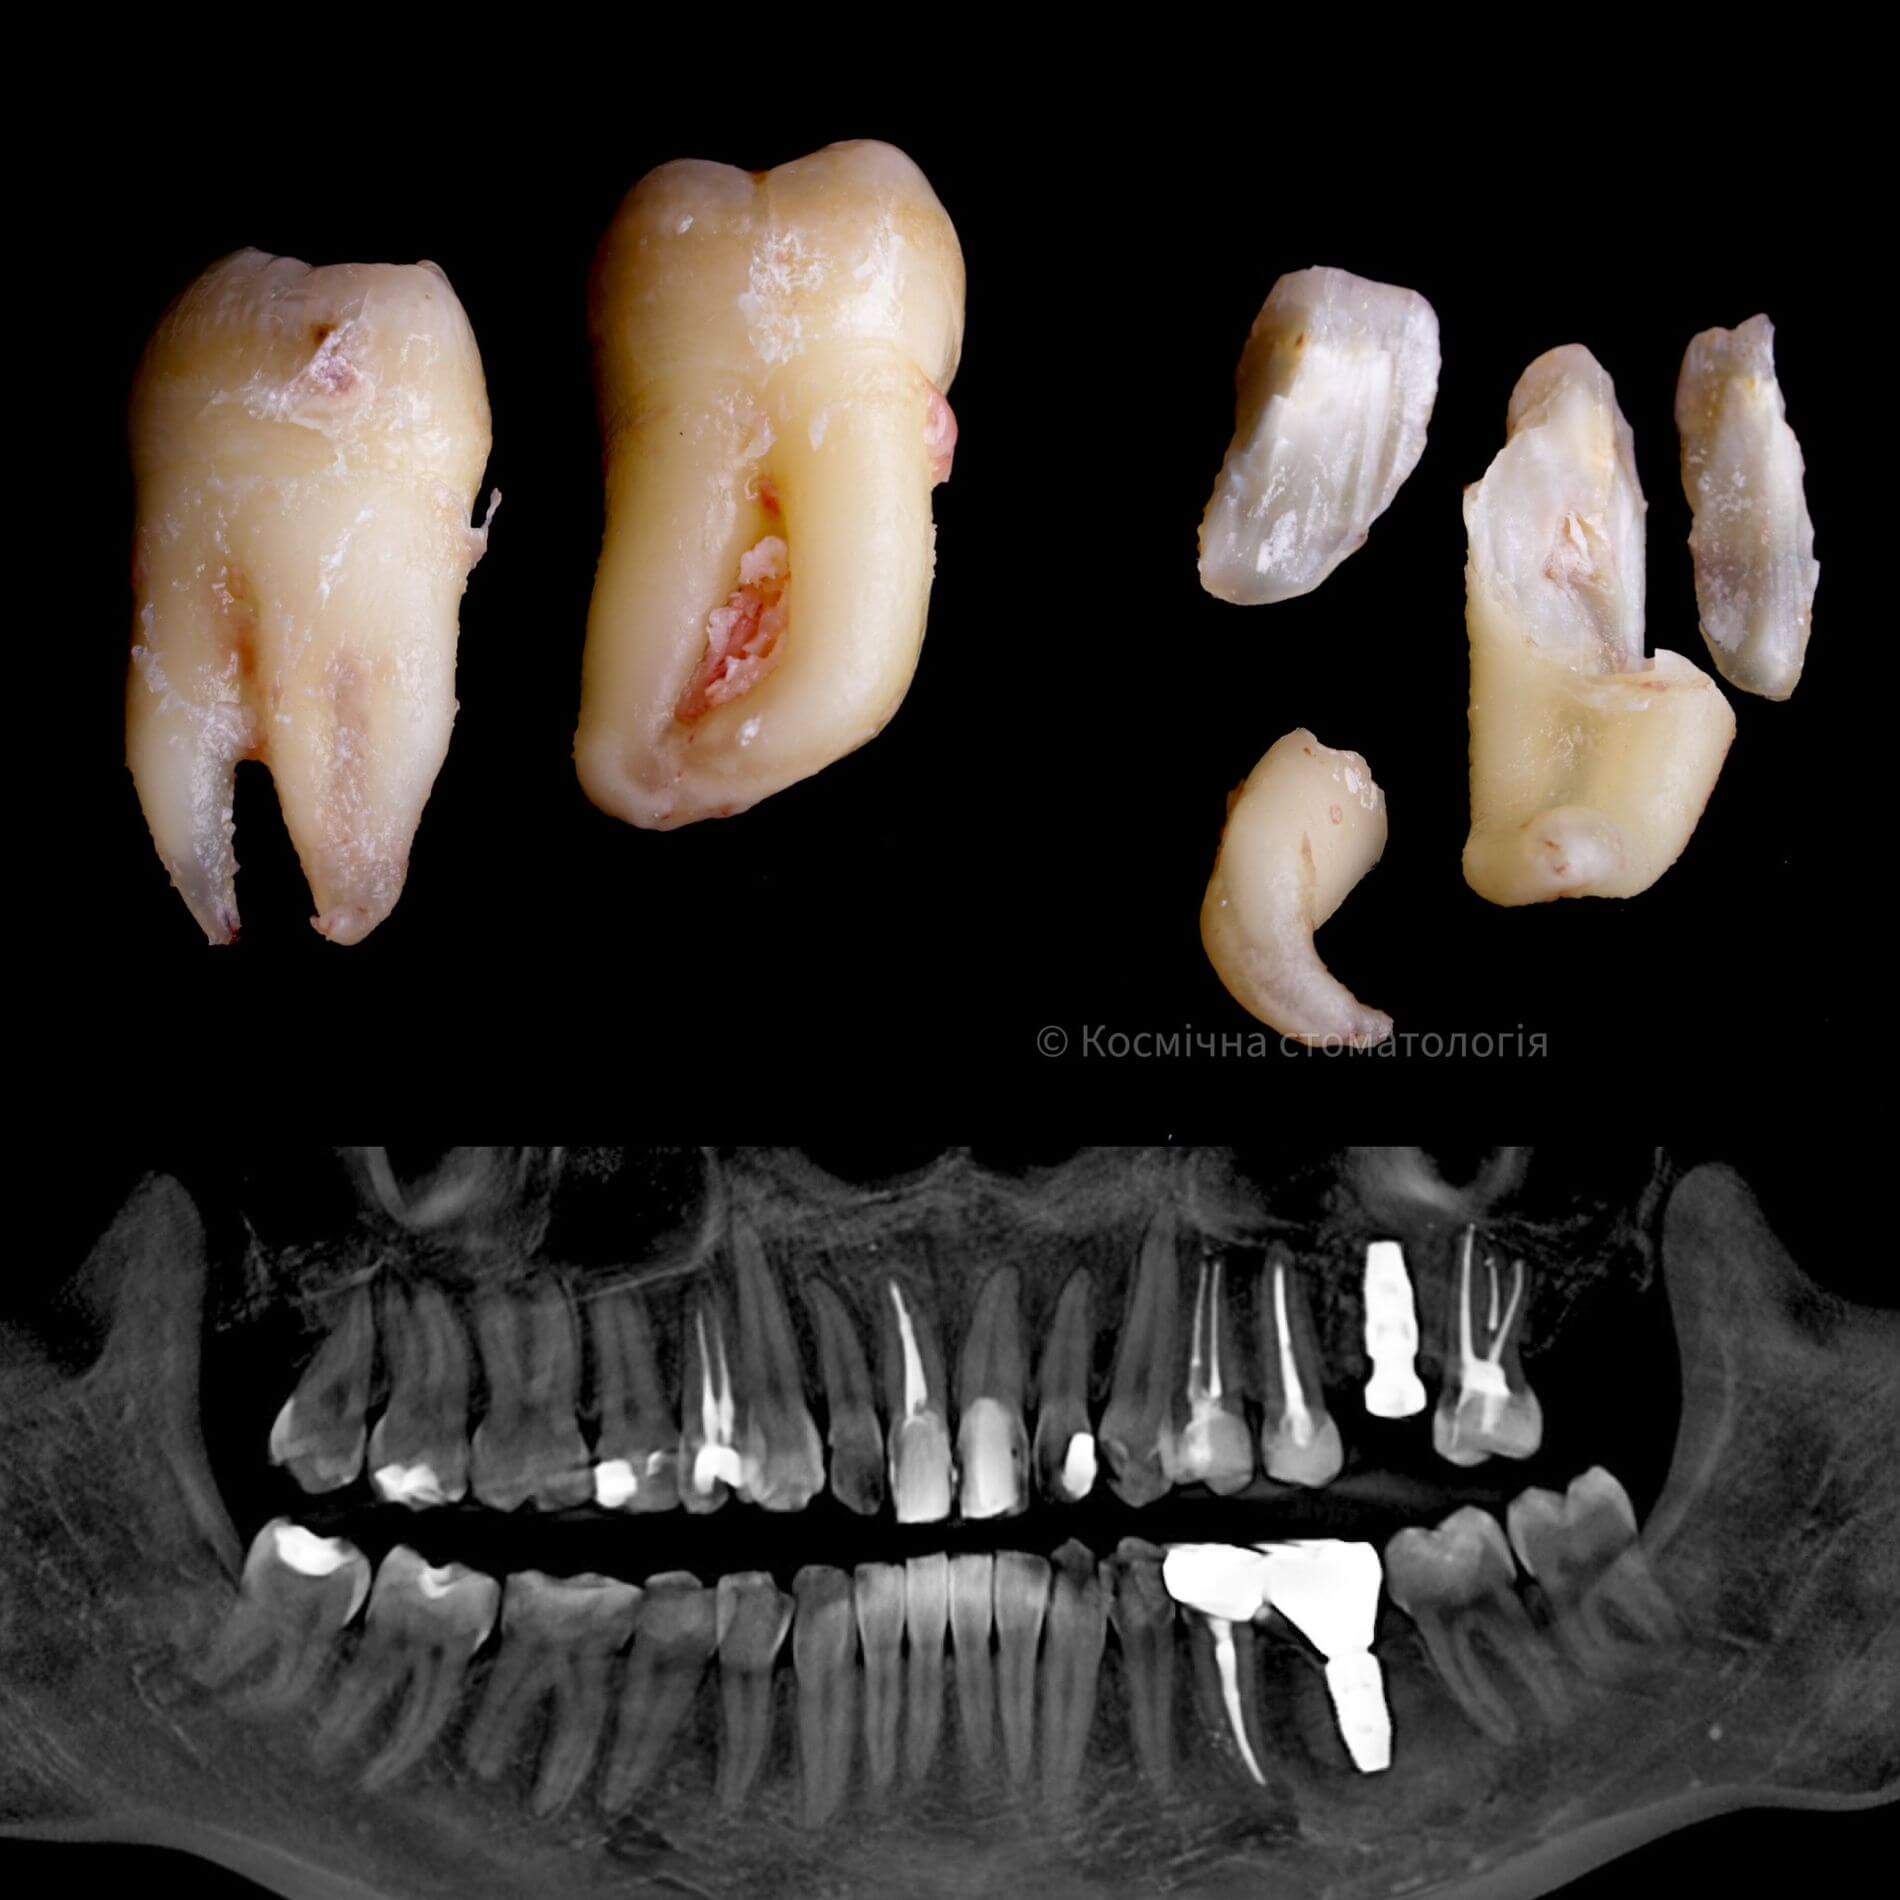

Галерея